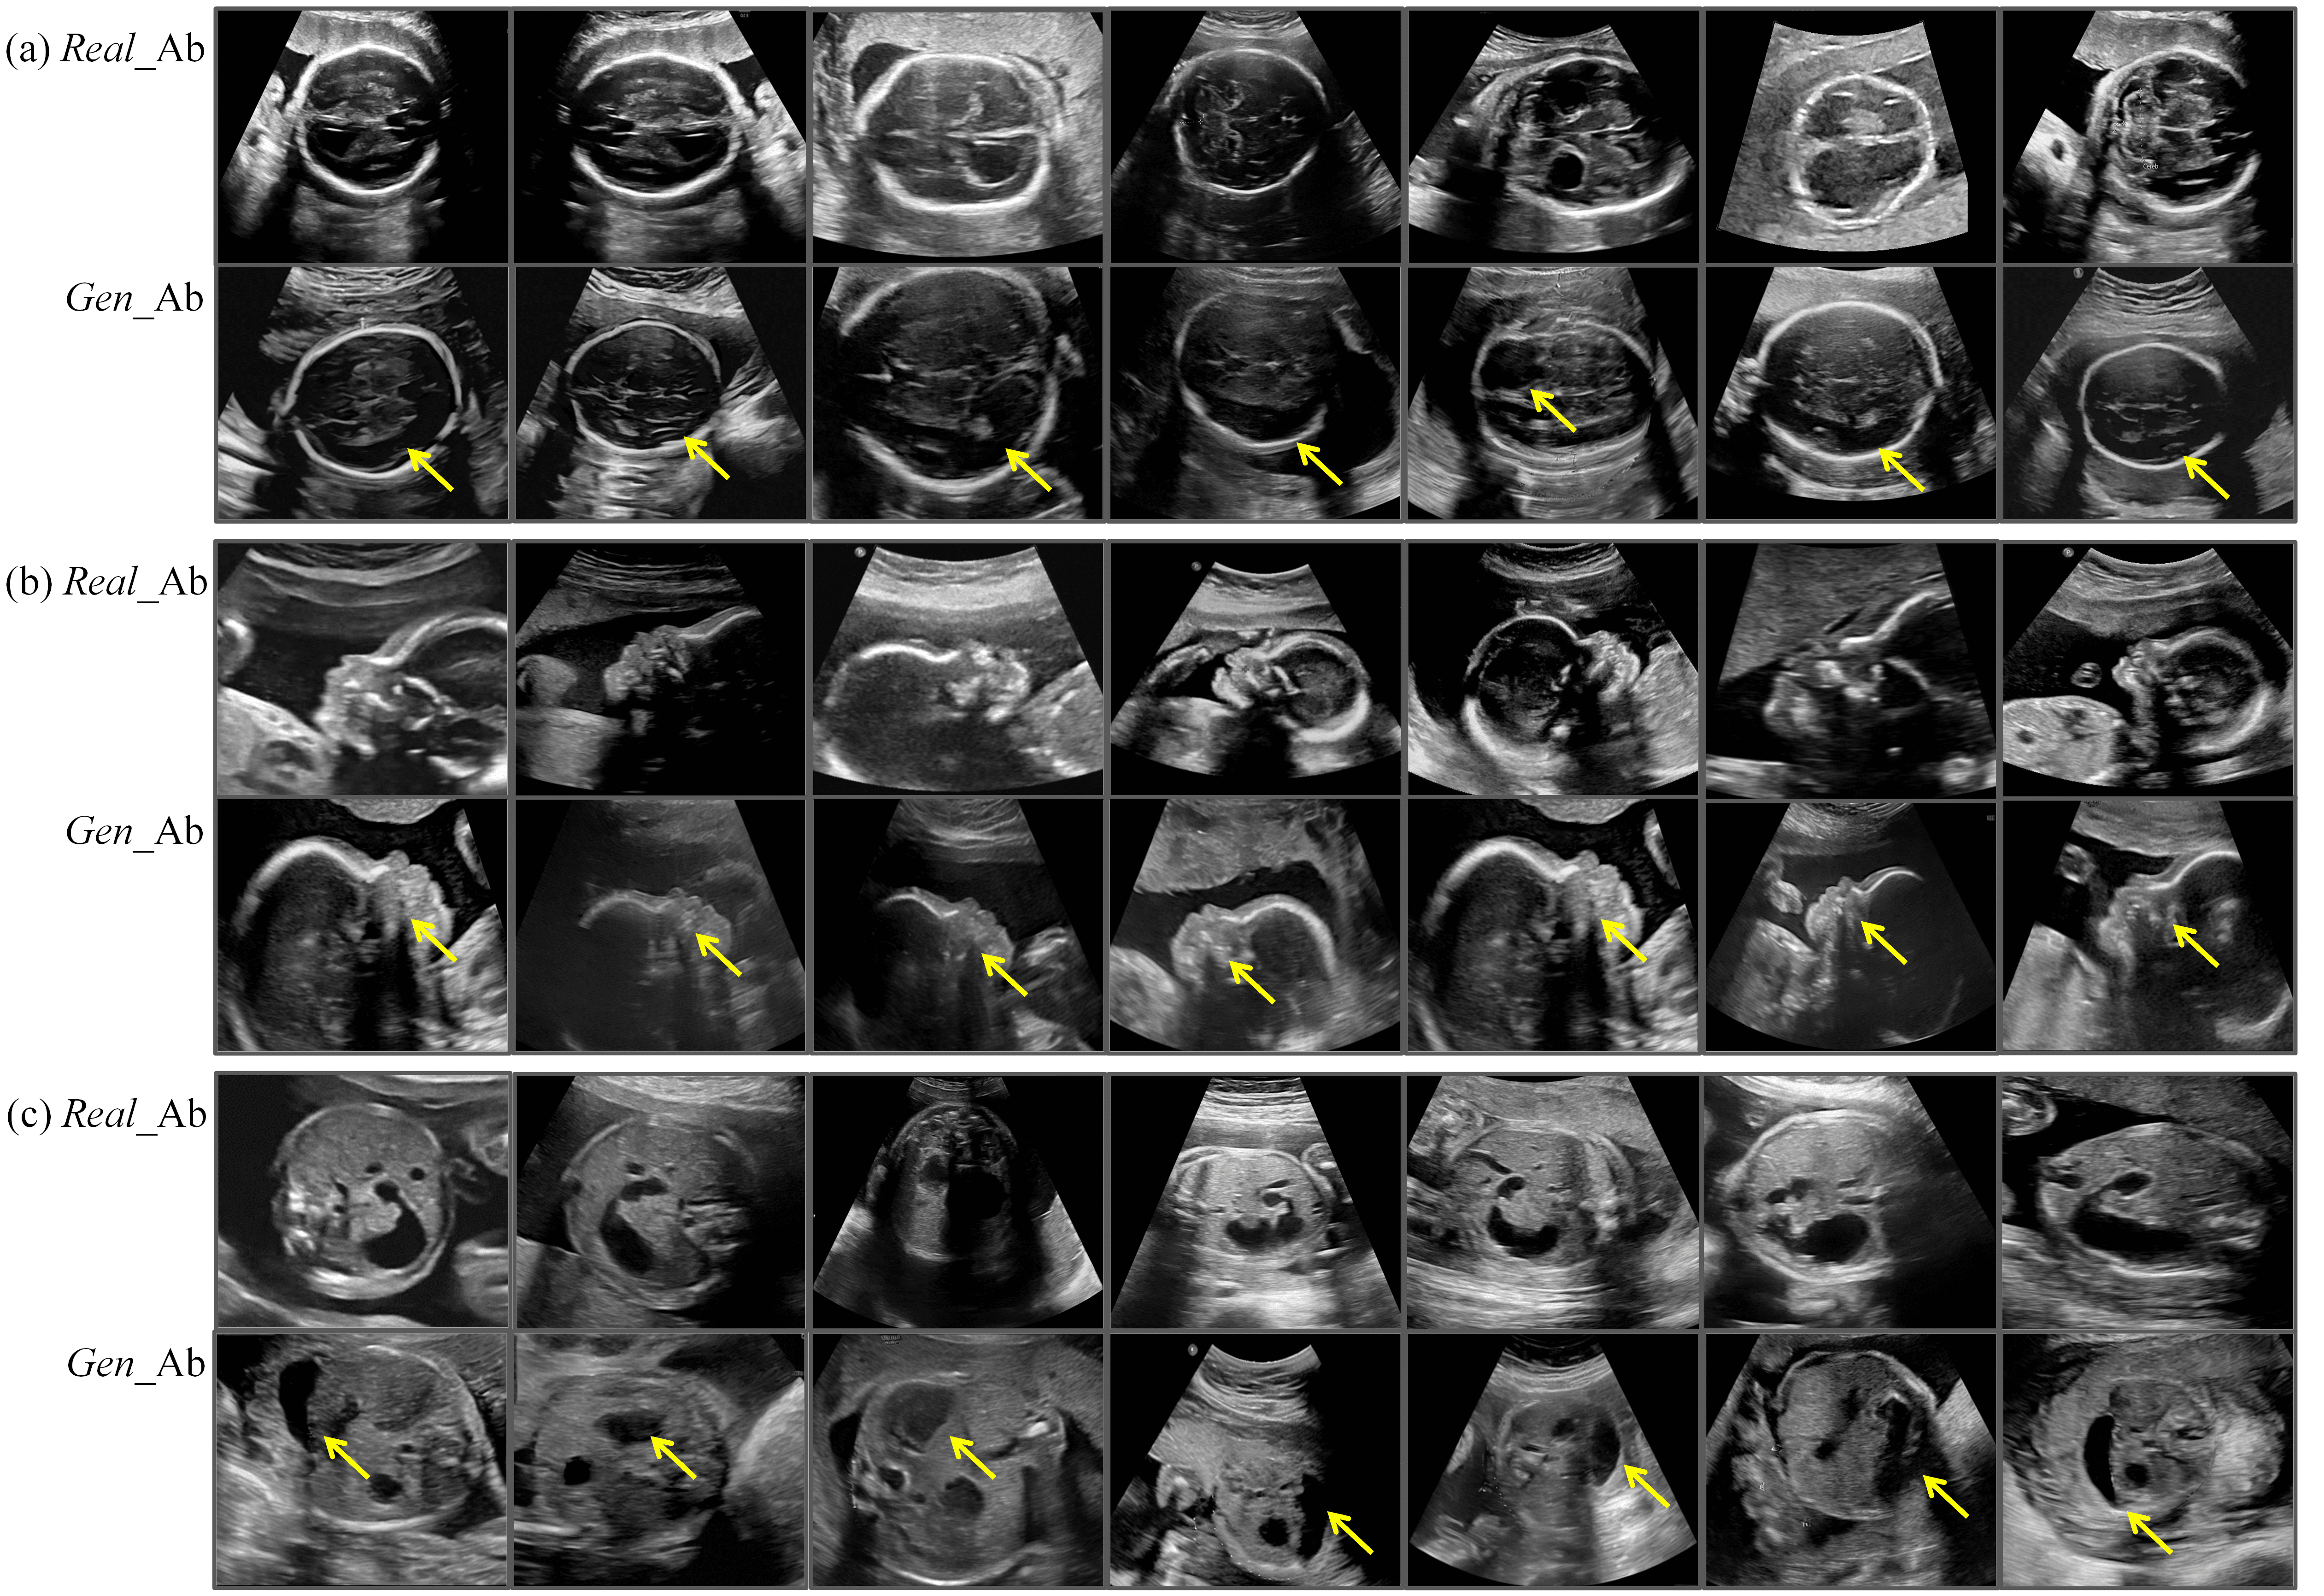

Figure 8: Real and generated abnormal fetal US images. (a) (b) (c) represent three different fetal US datasets. The first row displays a subset of real cases of hydrocephalus, the third row shows a subset of real cases of cleft lip and palate, and the fifth row presents a subset of real cases of duodenal atresia or stenosis. The second, fourth, and sixth rows correspond to abnormal samples generated by FetalFlex, where the yellow arrows indicate the anatomical structures that generate results similar to the real anomaly samples. Real_Ab: Real abnormal US images; Gen_Ab: Generated abnormal US images.

It is important to note that in actual clinical prenatal screening, the types of fetal anomalies are highly diverse, involving multiple anatomical structures and physiological systems. This complexity causes challenges in retrospective data collection owing to the difficulty in covering all possible types of anomalies. Therefore, the retrospectively collected multi-center real abnormal dataset has certain limitations regarding the representation of anomalies across different fetal planes. In detail, the dataset for the transverse thalamic plane contains only cases of hydrocephalus, the facial sagittal plane dataset includes only fetuses with cleft lip and palate, and the upper abdominal transverse plane dataset is limited to cases of duodenal atresia or stenosis. For this reason, we instructed FetalFlex to perform a high-quality synthesis of abnormalities for the anatomical and structural manifestation characteristics of the abovementioned diseases. We visualized the real clinical anomaly data collected alongside the abnormal samples generated by FetalFlex, as shown in Fig. 8. By adjusting the control conditions, FetalFlex was able to generate US images that closely resemble the abnormal in real cases, allowing our proposed method to achieve cross-domain generation at the image-level.

However, currently no standardized metrics exist that quantify FetalFlex’s controllable generation capabilities. Therefore, validation was conducted through visualization results and anomaly detection experiments. In the visualizations, we carefully presented the results generated under conditions where individual anatomical structures were altered, as shown in Fig. 10. Specifically, we applied image editing techniques, such as translation, rotation, scaling, and removal, to modify the control information for several small anatomical structures, simulating various fetal abnormalities that may occur in the real world. By integrating two-stage sampling strategy, the proposed FetalFlex framework accurately generates US images corresponding to the edited defect layouts without affecting the unedited anatomical structures. In the third row of Fig. 8, we showcase some real cases of cleft palate. The US image displays an interruption or discontinuity in the fetal palate, represented by an anechoic area. Similarly, the FetalFlex-generated cleft palate image exhibits an identical anechoic area in the palate, closely resembling the real case. This result demonstrates FetalFlex’s capability to capture fine anatomical details of the fetus and highlights its potential as a universal framework, capable of simulating a wide range of developmental abnormalities or malformations encountered during fetal examination.

In the visualized results of the general changes in anatomical structure shown in Fig. 8, we guided the global control information to generate images that closely resemble the US representations of real cases of malformation due to limitations imposed by the types of cases in our retrospective dataset. For example, the results synthesized by FetalFlex in the thalamic dataset can simulate the typical characteristics of ventricular enlargement in actual cases of hydrocephalus, specifically manifested as large areas of anechoic or hypoechoic regions, which appear black and represent the presence of fluid within the ventricles. Similarly, the “double bubble sign” is a typical feature of duodenal obstruction or stenosis in the abdominal dataset, appearing as two distinct anechoic or hypoechoic cystic structures (black) in the US image. FetalFlex has not encountered real cases; therefore, it can synthesize two black areas merely by altering the layout map but lacks the characteristic proximity of the double bubble observed in real cases. The synthesized results still play a positive role in model training during anomaly detection experiments; nevertheless, further improvements in the visual quality of medical images are required.